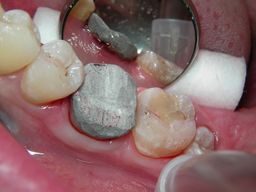

Die fertige Aufbaufüllung aus Amalgam. Der Zahn hat nun wieder ausreichend Wandhöhe. Erst jetzt ist die Voraussetzung für eine kofferdamdichte Wurzelkanalbehandlung erfüllt.

Nach Anlegen des Kofferdams wird die Zugangskavität durch die Aufbaufüllung hindurch in die Pulpakammer gebohrt. Jetzt kann sauber und trocken gearbeitet werden.